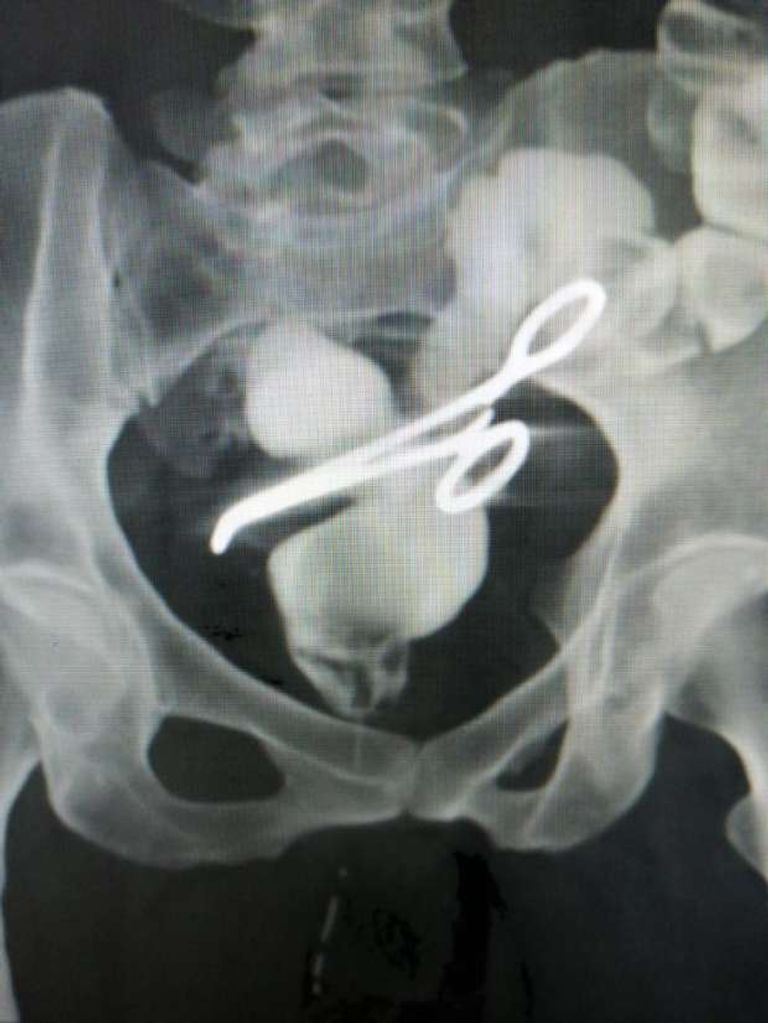

واستخرج الأطباء "جفت شرياني" من تجويف بطن سيدة في جراحة استمرت 5 ساعات، بعد معاناة وآلام مبرحة.

حضرت السيدة للعيادة الخارجية بمركز جراحة الجهاز الهضمي، وقابلت الدكتور أمجد فؤاد رئيس أقسام الجراحة بكلية الطب جامعة المنصورة، وتم الكشف على الحالة فوجد أن بها شيئًا غريبًا وغير معتاد ببطنها، فأجرى عليها أشعة ومناظير وفحوصات، فتبين وجود جسم معدني بمنطقة الحوض.

خضعت السيدة لعملية تحضير مكثفة وتدقيق في مركز جراحة الجهاز الهضمي بجامعة المنصورة، فتبين وجود ناسور بين المستقيم والمهبل، بسبب وجود جفت شرياني أصاب القولون والمستقيم والمثانة وعنق الرحم.

تم استخراج الجفت واسئتصال الأجزاء المصابة في جراحة مطولة استمرت 5 ساعات، بمشاركة فريق طبي كبير بمشاركة الدكتور محمد عبدالرازق مدرس الجراحة، والطبيب محمد الكامل والطبيب محمد أمجد، وبمشاركة فريق التخدير الدكتور أمجد زغلول، والدكتورة أماني طرباي والتمريض: ميادة الدسوقى، ماجدة رحب ونهلة أحمد، الفني: محمد السيد.